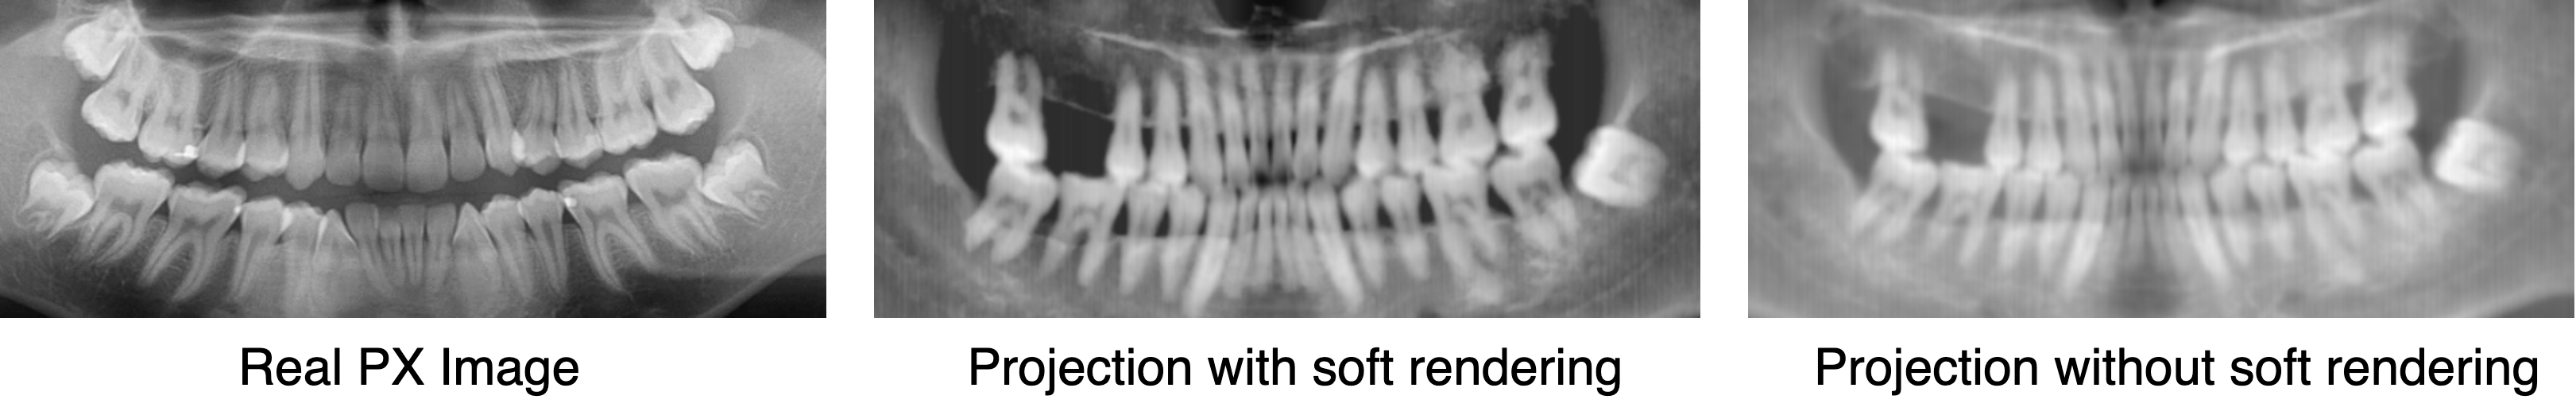

Figure 6: Comparison of different rendering methods in PX imaging. We can see that with soft rendering the generated PX image has a closer contrast with the real PX image (obtained from Internet). The real PX image looks more clear due to the high resolution of the PX machine.

where C=H(μair)𝐶𝐻subscript𝜇𝑎𝑖𝑟C=H(\mu_{air}). Comparisons among real PX image and simulated images generated by f()𝑓f(\cdot) and f^()^𝑓\hat{f}(\cdot) can be seen in Fig 6, where PX images simulated by f^()^𝑓\hat{f}(\cdot) has a more closer contrast as real images.